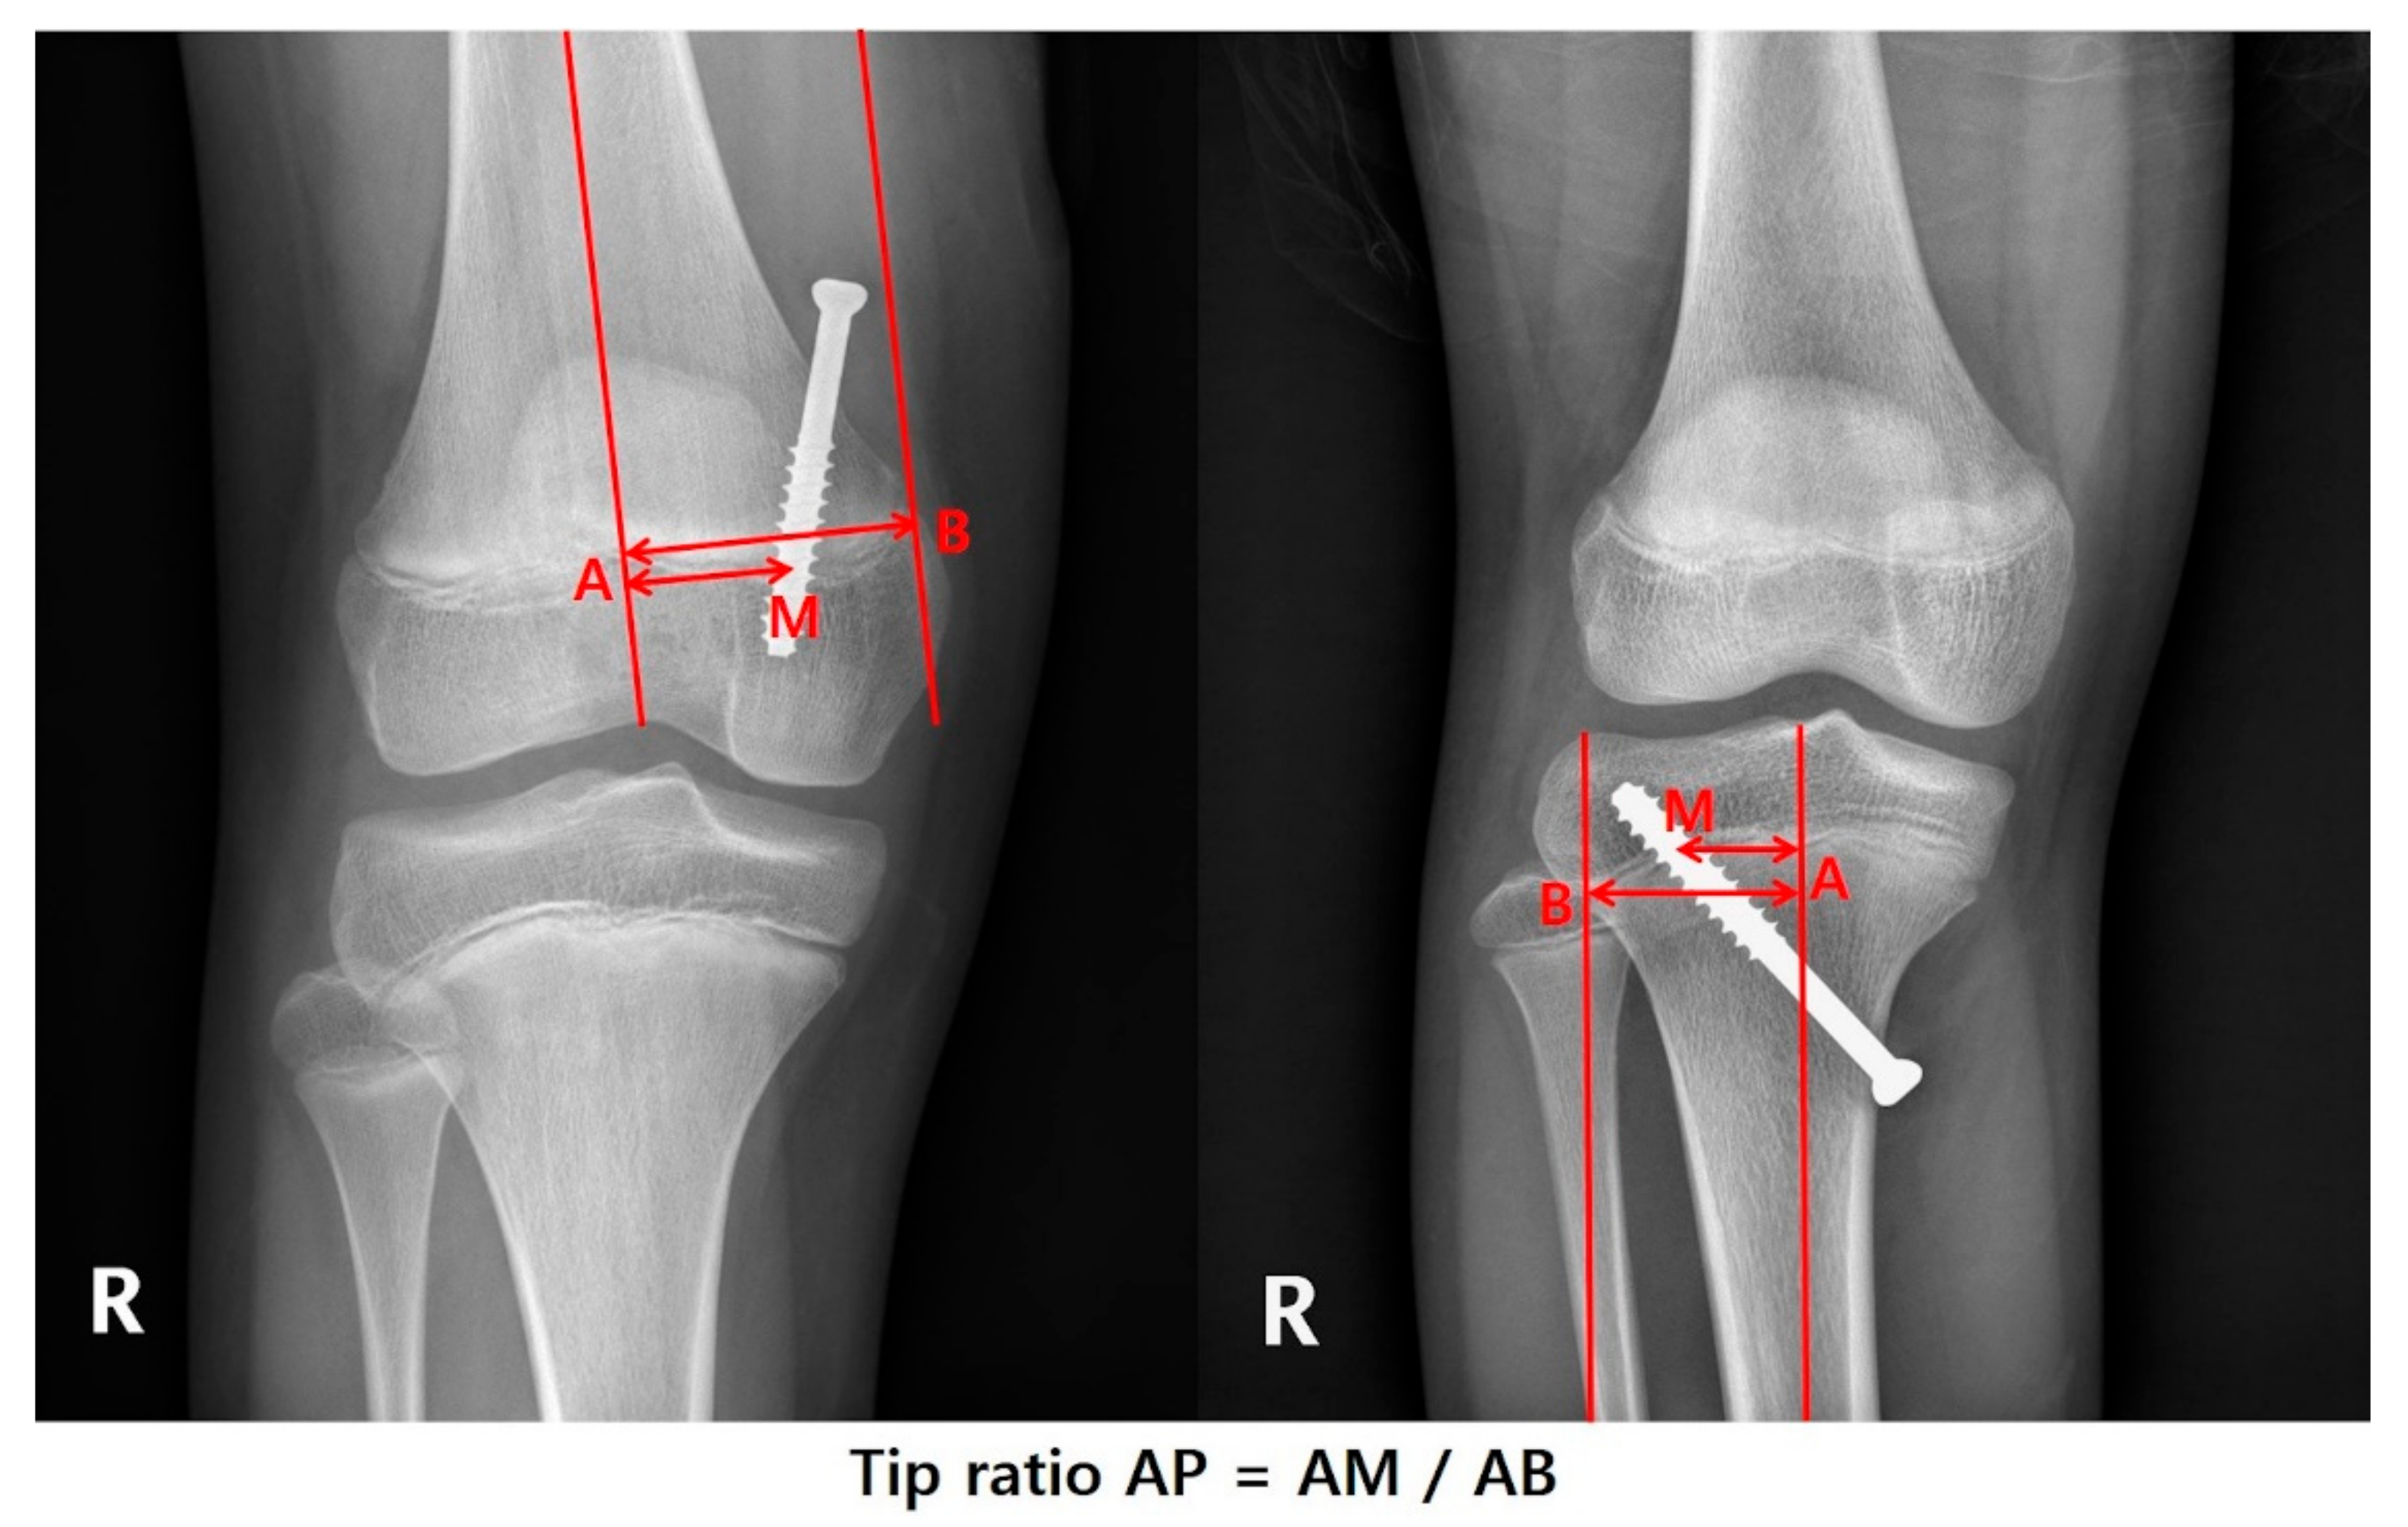

| Tip ratio AP | 0.64 ± 0.1 | 0.64 ± 0.09 | 0.63 ± 0.11 | 0.948 |

| Tip ratio AP | −1.578 (−2.808 to −0.348) | −0.304 | 0.065 | |||

| Tip ratio Lat | −1.313 (−2.250 to −0.377) | −0.329 | 0.008 | |||

| Tip ratio AP | −3.765 (−9.865 to 2.336) | −0.152 | 0.231 | |||

| Tip ratio Lat | −2.767 (−7.460 to 1.926) | −0.145 | 0.252 | |||

| * Tip ratio AP | Valgus | −2.519 (−4.045 to −0.993) | −0.447 | 0.053 | −2.909 (−4.273 to −1.544) | −0.516 | 0.150 |

| ** Tip ratio Lat | Valgus | −0.203 (−1.740 to 1.333) | −0.040 | 0.797 | |||

| * Tip ratio AP | Valgus | −6.951 (−15.341 to 1.438) | −0.243 | 0.112 | −9.375 (−16.121 to −2.630) | −0.328 | 0.100 |

| ** Tip ratio Lat | Valgus | 3.059 (−4.684 to 10.802) | 0.119 | 0.443 | |||